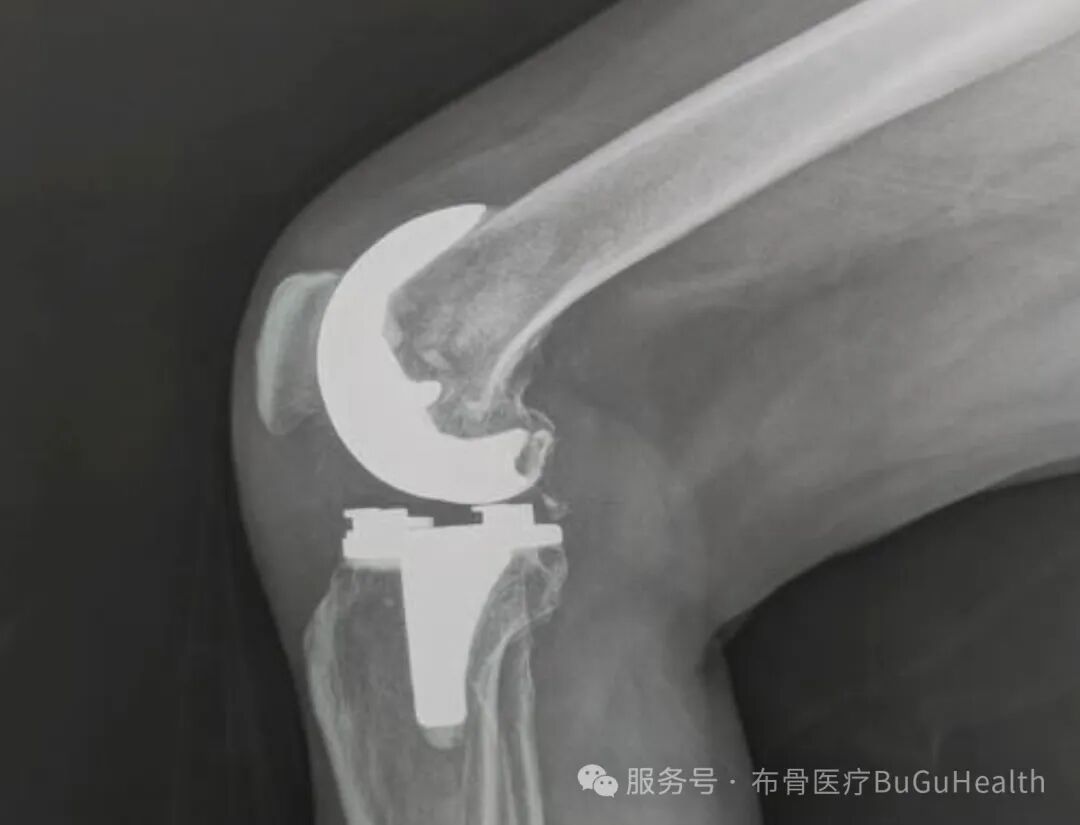

单腿站立:尝试用患肢单腿站立,保持平衡,每次30秒,每天3~4组。神经肌肉训练:包括单腿深蹲、侧向行走等,增强肌肉力量和关节稳定性3、药物治疗:非甾体抗炎药(NSAIDs):如布洛芬、双氯芬酸等,可有效缓解疼痛和炎症。关节腔注射:透明质酸(HA)注射可以改善关节润滑,减轻疼痛。4、手术治疗:对于症状严重、保守治疗无效的患者,可以考虑手术治疗,如胫骨高位截骨术(HTO)或膝关节置换术。胫骨高位截骨术通过改变下肢力线,减轻关节压力,延缓关节炎进展。2.适度运动:选择对膝关节压力较小的运动,如游泳、骑自行车。3.加强肌肉训练:增强膝关节周围肌肉的力量,尤其是股四头肌。4.避免外伤:运动时注意保护膝关节,避免剧烈冲击。如果你有膝关节疼痛、肿胀或活动受限的症状,建议及时就医,明确诊断并采取合适的治疗措施。记住,保护膝关节,从日常做起!希望这篇文章能帮助大家更好地了解膝关节骨关节炎。如果你觉得有用,别忘了点赞、收藏和转发哦!